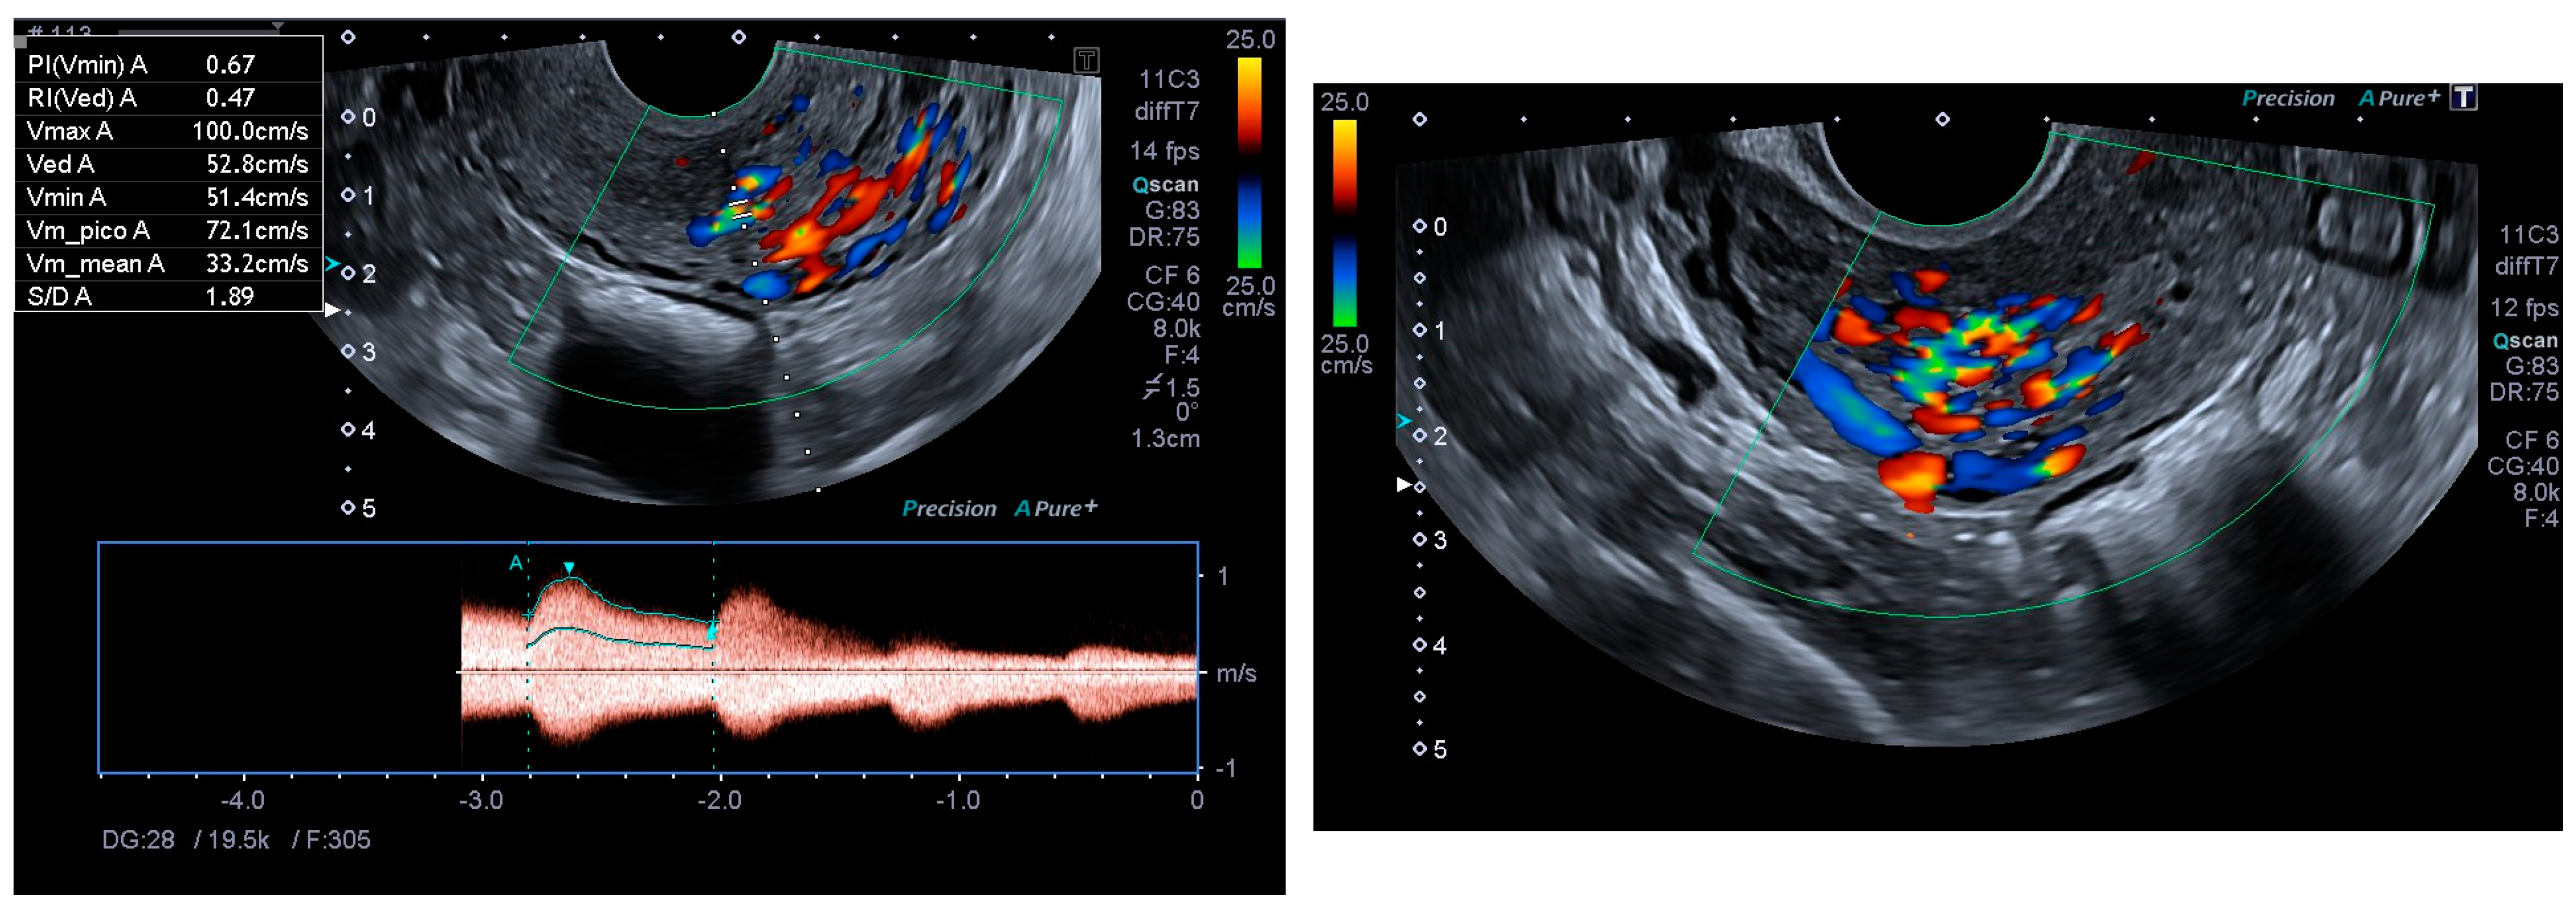

Finally, the vascular surgeons ruled out selective arterial embolisation because the size of the lesion made complete and effective embolisation impossible. Conservative treatment with combined hormonal contraceptives was chosen because the patient’s reproductive desires were not fulfilled. After four months of being asymptomatic and under treatment with combined hormonal contraceptives, the patient presented for follow-up, at which time no AVM was observed on the ultrasound, either in B-mode or colour Doppler (Figure 5 and Figure 6).

Figure 5. Linear endometrium after conservative treatment for 4 months.